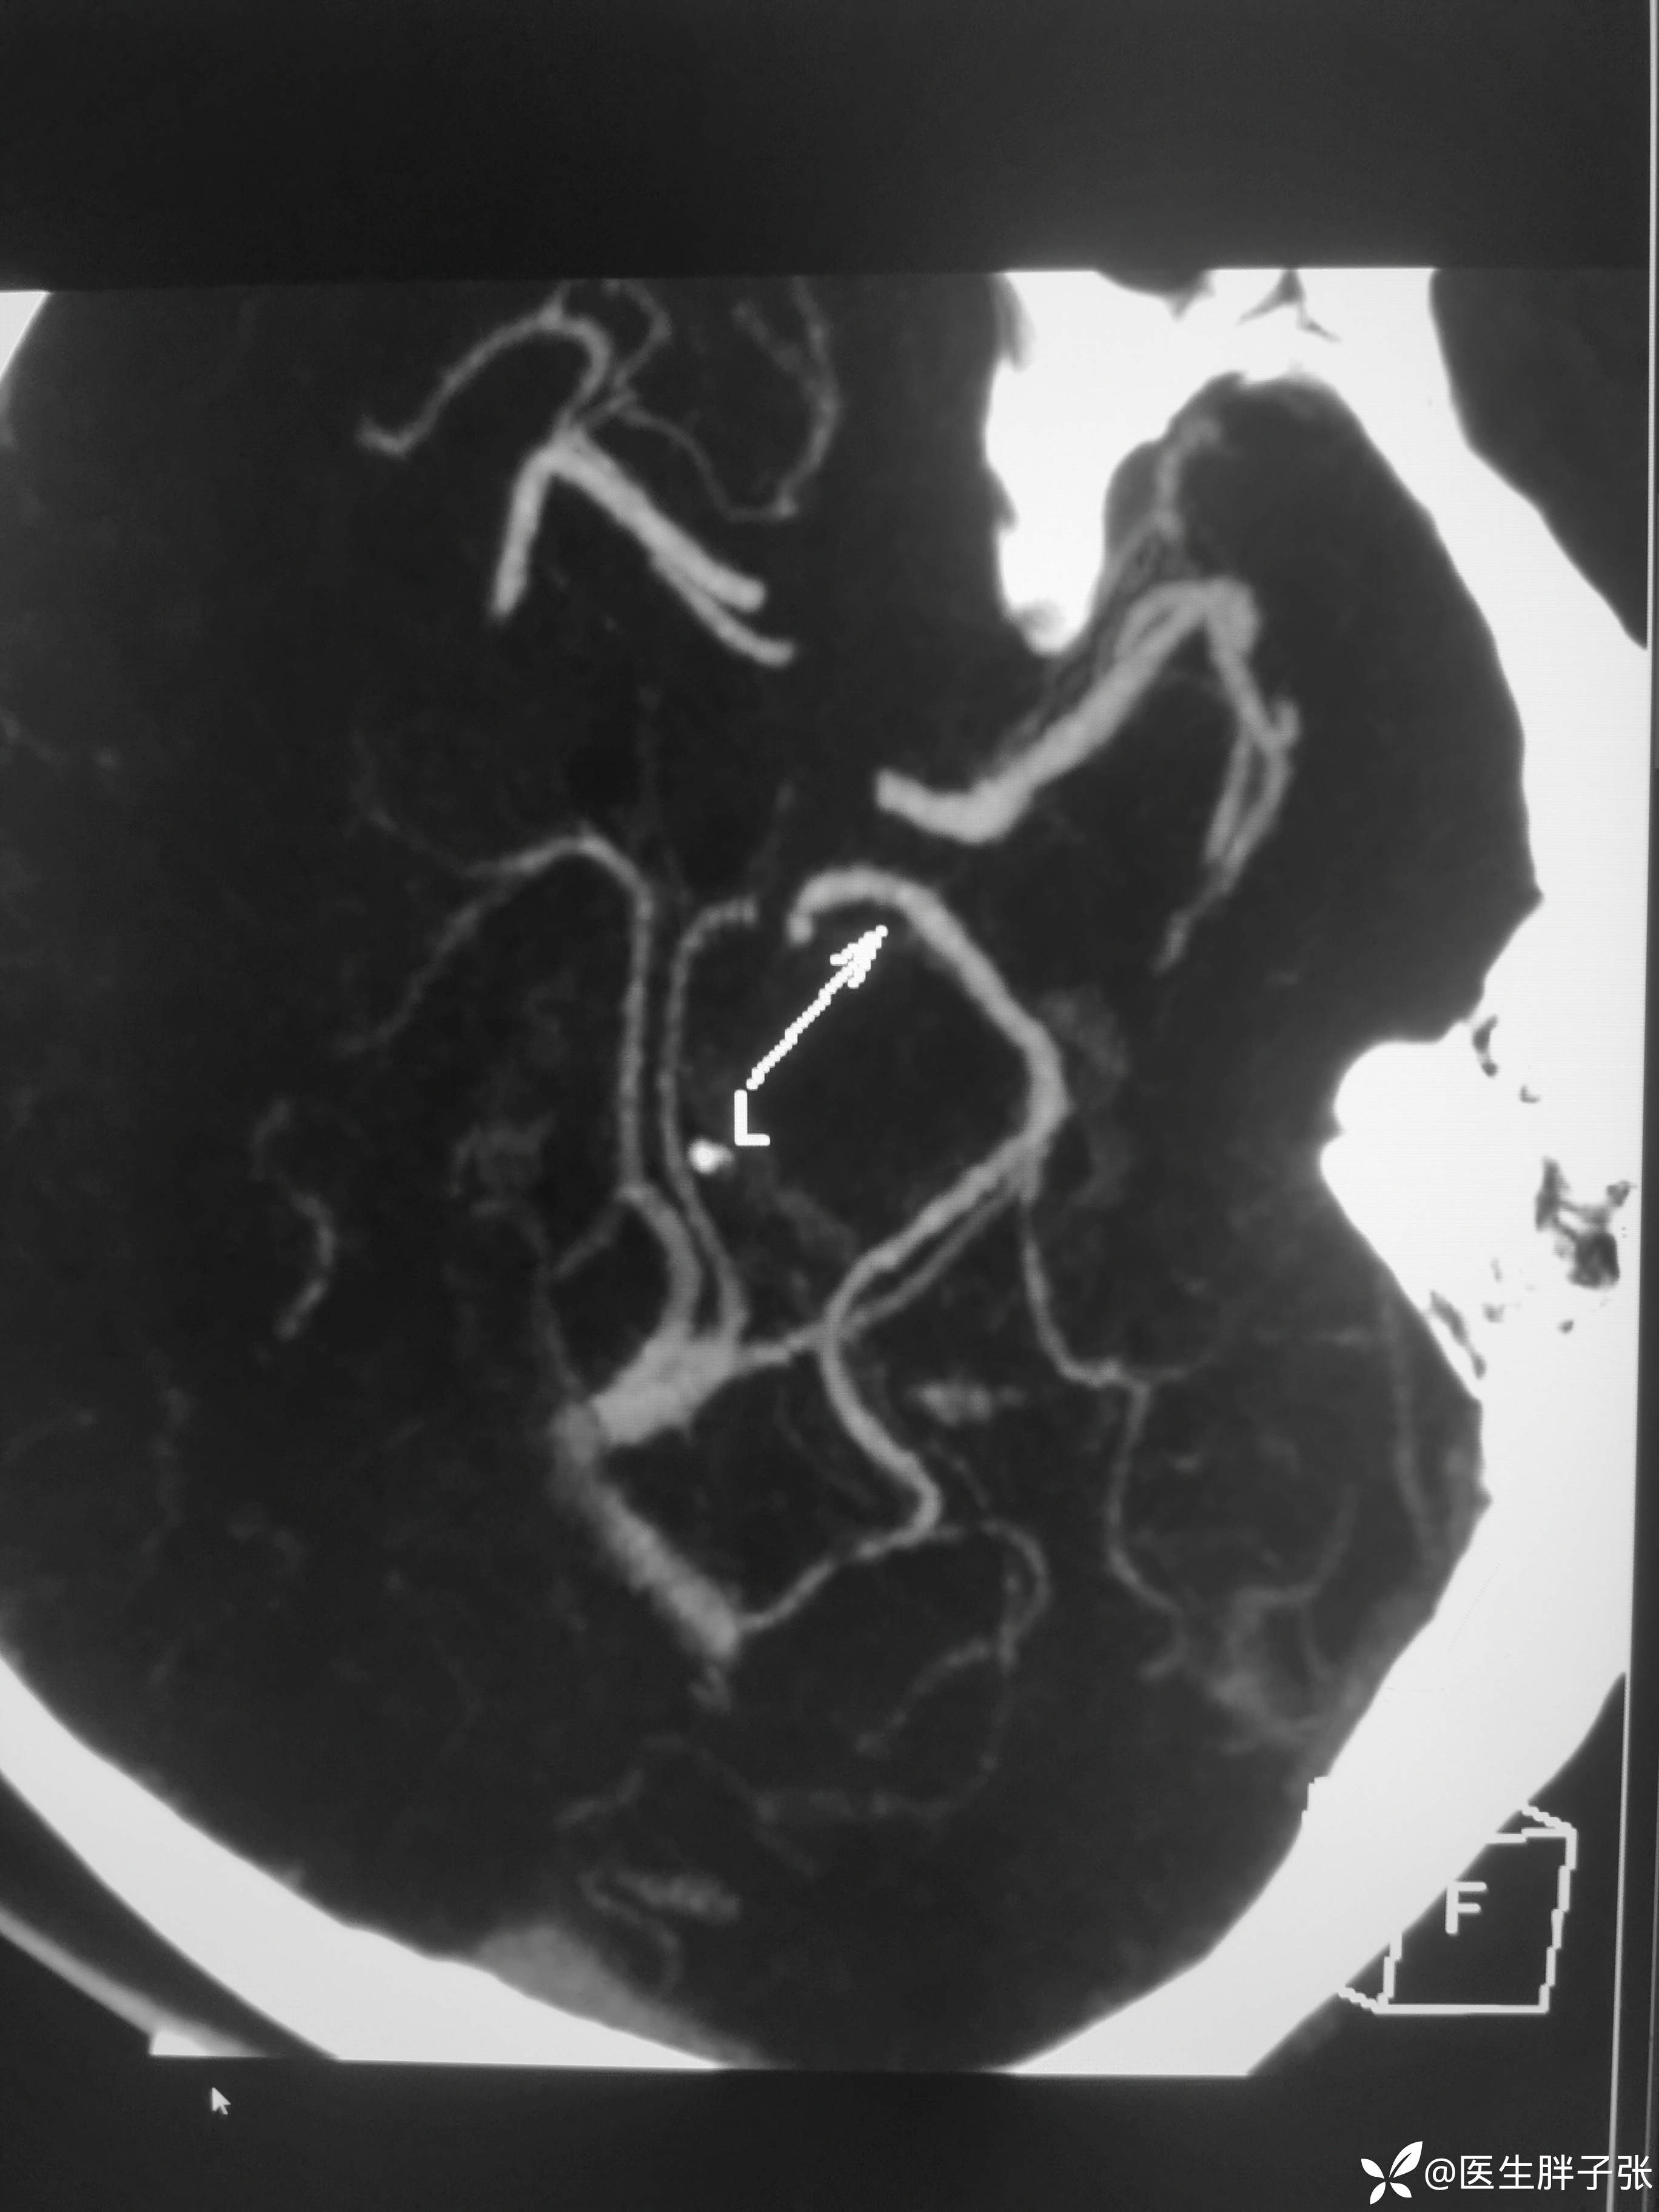

头颈部CTA